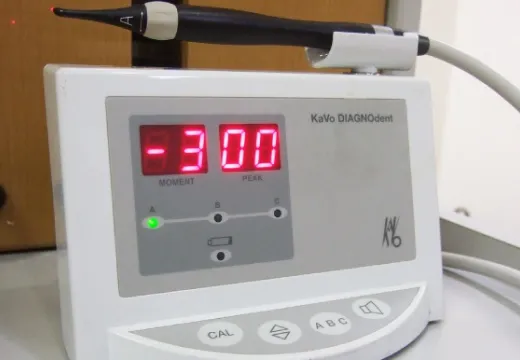

ダイアグノデント

虫歯の程度をレーザーで数値化する器具、治療の必要性を無痛的に正確に診断します。

ダイアグノデントペン

こちらの新型では、歯の間を計測することが可能です。従来型と併用して使っています。